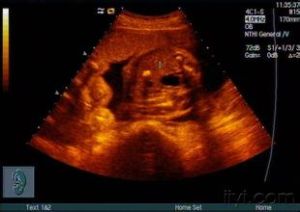

⑤先天發育形成,子宮內的胎兒有肝內鈣化灶形成,常合併先天畸形,發現率為0.057%。

肝內鈣化灶CT解析度高,顯示鈣化清晰,主要用於B超難於鑑別肝內鈣化灶,尤其懷疑肝內轉移瘤時。多數肝內鈣化灶是在正常體檢時偶然被發現,對於肝內單個或多個孤立無融合的鈣化灶,無自覺症狀和體徵,肝臟大小和形態無異常者,可能與先天發育、營養不良、鈣磷代謝紊亂或損傷等因素有關,也可能是某些病變,如肝內膽管結石、肝膿腫或肝臟創傷癒合後改變。這類肝內鈣化灶的B超圖像特點是:呈“品字”或“等號”狀分散的強回聲,走行於膽管腔外,後方大多無聲影或淡的聲影,同時無肝內膽管擴張。對這類肝內鈣化不需治療,為了慎重起見,對於這類鈣化灶可以隨訪觀察達2~3年,每3~6月複查B超檢查。 鈣化灶B超圖像特點